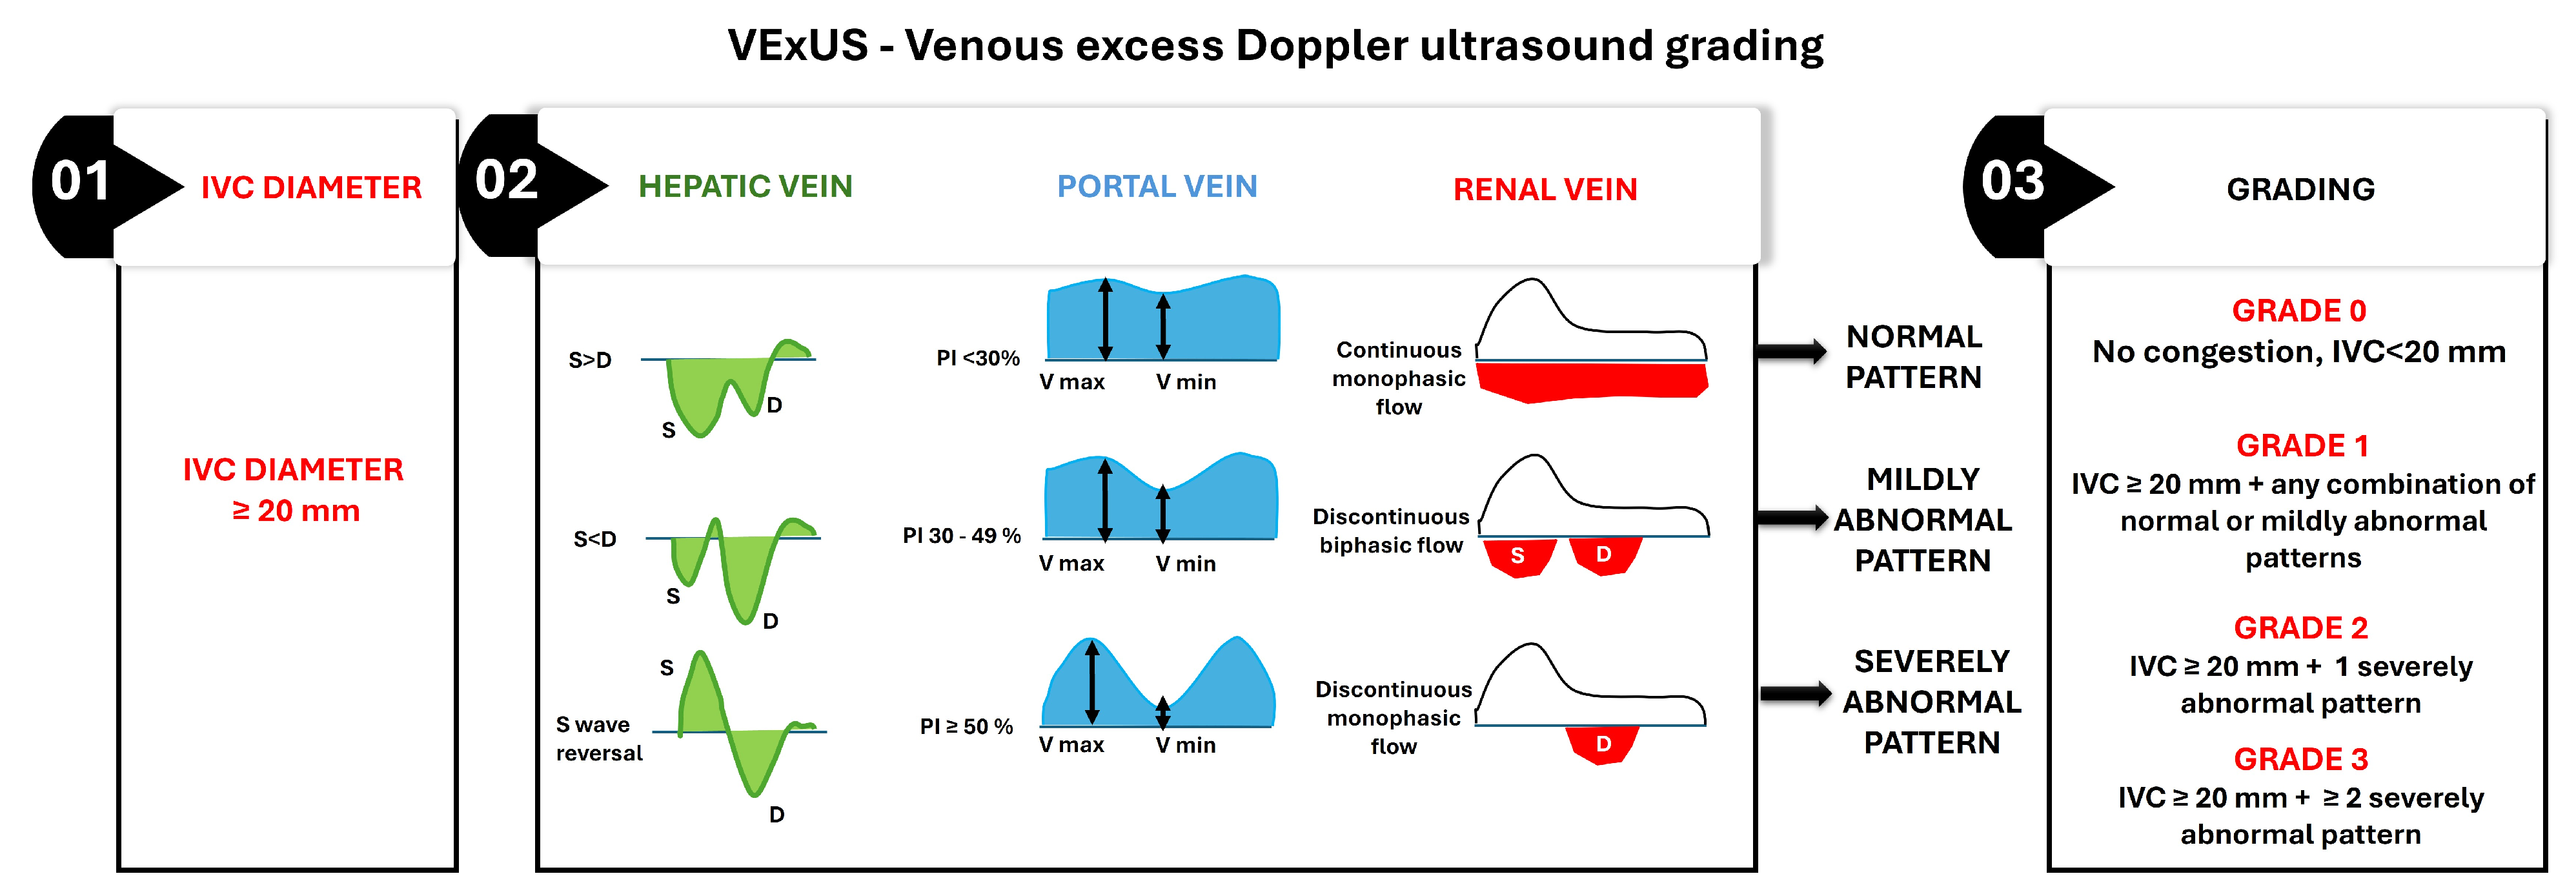

- Estimation of right ventricular (RV) filling pressures

- Inferior vena cava evaluation

- Doppler Flow in the Hepatic Veins and the Portal veins

- Ultrasonographic Evaluation of Intrarenal Venous Flow

Clinical Practice Scores

- IVC Diameter Assessment—The assessment begins with measuring the IVC diameter at its widest point during quiet respiration in the subcostal view. An IVC diameter ≥ 20 mm indicates elevated CVP, which is often associated with systemic venous congestion. This finding necessitates further evaluation of venous Doppler waveforms to confirm and grade the severity of congestion;

- Hepatic Vein Doppler Waveform Analysis—The hepatic vein Doppler waveform typically exhibits triphasic flow, with a dominant systolic (S) wave under normal conditions. As venous congestion worsens, the S wave diminishes relative to the diastolic (D) wave, and in severe cases, S wave reversal occurs;

- Portal Vein Pulsatility Index (PVPI)—The portal vein normally demonstrates continuous flow with minimal pulsatility. It increases with elevated CVP due to direct transmission of right atrial pressure, and a PVPI ≥ 50% indicates severe portal venous congestion;

- Renal Vein Doppler Waveform Analysis—The renal vein Doppler waveform is normally continuous and monophasic. With increasing venous congestion, the waveform becomes discontinuous or biphasic, and, in severe cases, it transitions to monophasic diastolic flow only;

- Grading system: The final VExUS grade is assigned based on the combination of IVC diameter and the severity of Doppler abnormalities in the hepatic, portal, and renal veins:

- Grade 0: IVC diameter < 20 mm, with no Doppler abnormalities, indicating no congestion;

- Grade 1: IVC diameter ≥ 20 mm with any combination of normal or mildly abnormal venous Doppler patterns;

- Grade 2: IVC diameter ≥ 20 mm with one severely abnormal venous Doppler pattern (S wave reversal in the hepatic vein, PVPI ≥ 50% in the portal vein, or discontinuous monophasic flow in the renal vein);

- Grade 3: IVC diameter ≥ 20 mm with two or more severely abnormal venous Doppler patterns.

| Inferior Vena Cava (IVC) Ultrasound | Evaluates right-sided filling pressures. | Useful in assessing volume status and guiding therapy. | Dilated IVC with reduced collapsibility indicates elevated CVP. | Predicts rehospitalization risk based on IVC diameter and collapsibility. |

| Hepatic Vein Ultrasound | Assesses right heart hemodynamics. | Provides insights into hepatic congestion and right atrial pressure. | Changes in waveform patterns correlate with congestion severity. | Predicts cardiac events based on hepatic venous stasis index. |

| Portal Vein Ultrasound | Evaluates systemic venous congestion. | Useful in assessing portal vein pulsatility and congestion severity. | PVPI ≥ 50% indicates severe systemic congestion. | Predicts outcomes based on changes in PVPI. |

| Renal Vein Ultrasound | Assesses renal hemodynamics and venous congestion. | Useful in identifying patients at risk of complications. | Discontinuous flow patterns indicate severe congestion. | Predicts outcomes based on improvement in renal venous Doppler parameters. |

- Landi, I.; Guerritore, L.; Iannaccone, A.; Ricotti, A.; Rola, P.; Garrone, M. Assessment of venous congestion with venous excess ultrasound score in the prognosis of acute heart failure in the emergency department: A prospective study. Eur. Heart J. Open 2024, 4, oeae050. [Google Scholar] [CrossRef] [PubMed]

- Rinaldi, P.M.; Rihl, M.F.; Boniatti, M.M. VExUS Score at Discharge as a Predictor of Readmission in Patients with Acute Decompensated Heart Failure: A Cohort Study. Arq. Bras. Cardiol. 2024, 121, e20230745. [Google Scholar] [CrossRef]

- Sovetova, S.; Charaya, K.; Erdniev, T.; Shchekochikhin, D.; Bogdanova, A.; Panov, S.; Plaksina, N.; Mutalieva, E.; Ananicheva, N.; Fomin, V.; et al. Venous Excess Ultrasound Score Is Associated with Worsening Renal Function and Reduced Natriuretic Response in Patients with Acute Heart Failure. J. Clin. Med. 2024, 13, 6272. [Google Scholar] [CrossRef]

- Koratala, A.; Romero-González, G.; Soliman-Aboumarie, H.; Kazory, A. Unlocking the potential of VExUS in assessing venous congestion: The art of doing it right. Cardiorenal Med. 2024, 14, 350–374. [Google Scholar] [CrossRef]

- Beaubien-Souligny, W.; Rola, P.; Haycock, K.; Bouchard, J.; Lamarche, Y.; Spiegel, R.; Denault, A.Y. Quantifying systemic congestion with Point-Of-Care ultrasound: Development of the venous excess ultrasound grading system. Ultrasound J. 2020, 12, 16. [Google Scholar] [CrossRef] [PubMed]